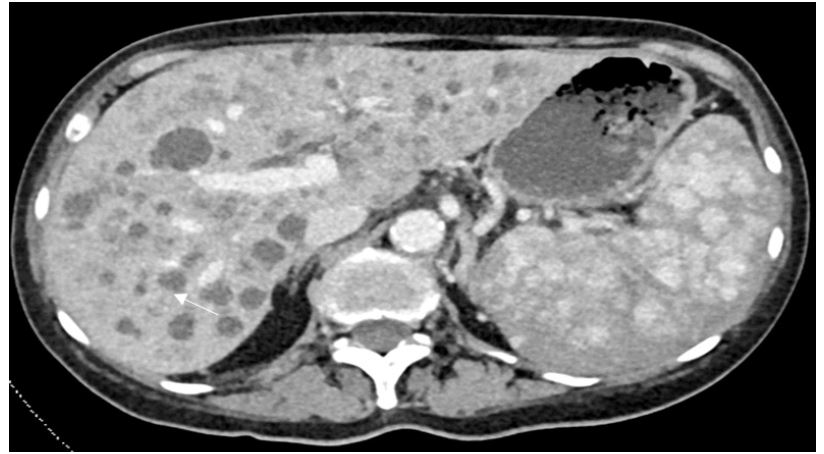

Computer tomography of the abdomen showed multiple low-density lesions of the liver, some with soft tissue attenuation but without enhancement, and borderline splenomegaly was also noted with mottled splenic enhancement. Multiple sclerotic bone lesions were noted (Figure 1).

On a CT scan, the spleen demonstrated borderline enlargement, measuring 12 cm and contained multiple hypodense lesions. There were also innumerable liver lesions, some of which contained non-enhancing foci of internal hyperdensity. Extensive tiny sclerotic metastases were noted in the axial and appendicular skeleton.

Figure 1: Axial CT scan image demonstrating a mottled appearance to the spleen and multiple liver hypodense lesions, some of which contain internal hyperdensity (white arrow)